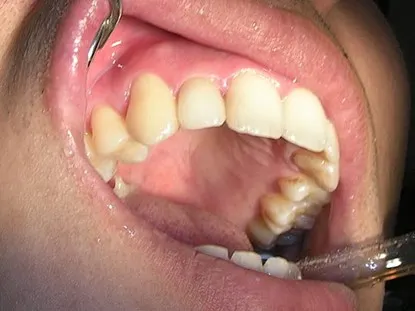

<<三年又三個月前 為陳先生裝#12 Cap-Lock>>

修形、排齦後取模、比色,有蛀牙同時幫他用樹脂填補